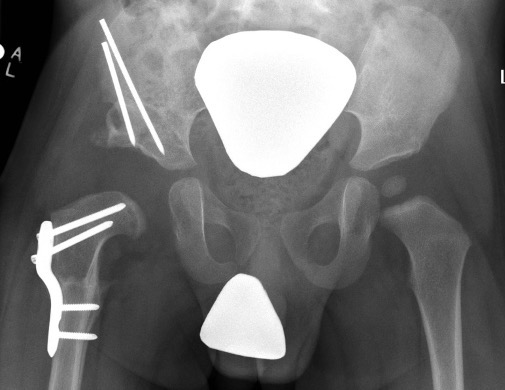

Salter complete osteotomy